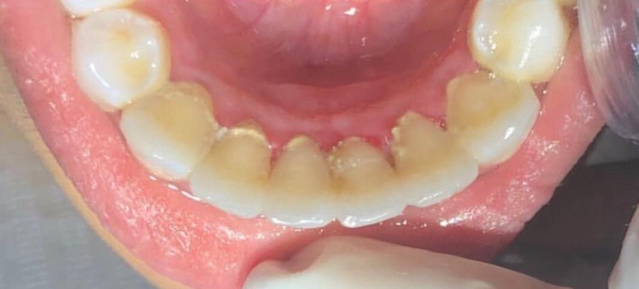

resina composta em dente anterior

curso de restaurações estéticas em resina composta

realidade clínica: resina composta